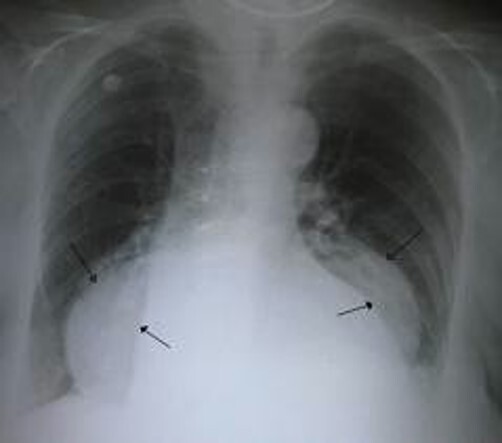

hiatal hernia

A

-10% of pts

-heartburn

-sudden regurgitation

-burping

-pain on swallowing hot fluids

-feeling of food stuck in esophagus

-MC- overwt middle aged women and elderly

-pregnancy

-type 2 GEJ stays below diaphragm

-dx-

-barium swallow

-endoscope

-radiograph

-Tx-

-no tx if no symptoms

-wt loss

-eat small meals frequently

-stop smoking

-antacids

-avoid hot, spicy, gassy drinks

-if GERD, failure of tx, large, complications (stricture, ulceration, bleeds) -> surgery for type 1

-all types except type 1 -> nissen fundoplication or hiatoplasty